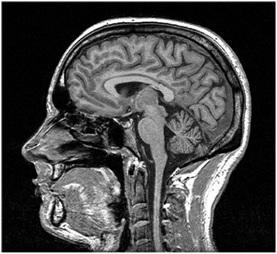

MRI stands for Magnetic Resonance Imaging. This technology relies on magnetism. It’s a more recent advancement compared to CT scans. MRI uses magnetism to create a 3D image of the body’s interior.

Similar to CT scanners, MRI machines have a moving platform. Patients lie down on this platform and are moved into a narrow cylinder. Magnets within the cylinder generate a strong magnetic field around the patient’s body. The cylinder is somewhat narrower compared to CT scanners. It’s crucial to remove all metallic objects from the body before an MRI scan. MRI scans can take around 30 minutes to complete.